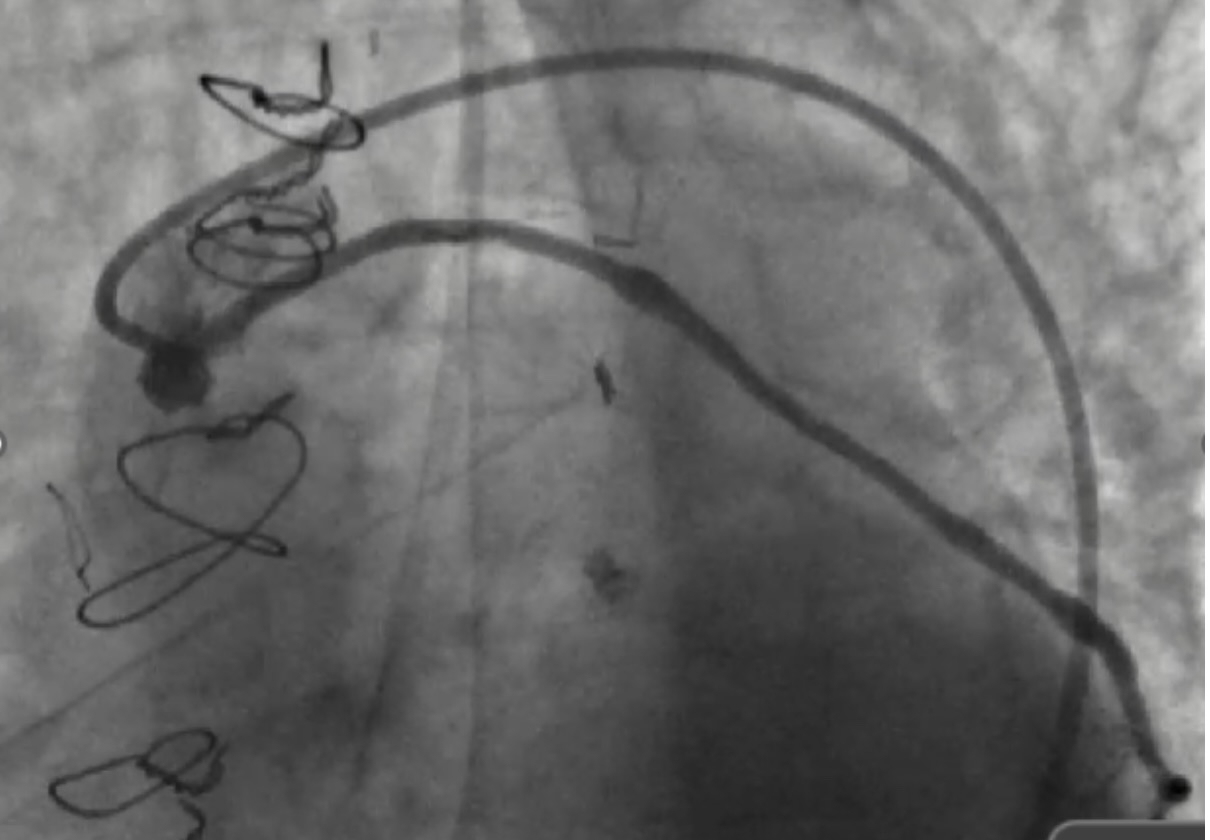

After shared decision-making, high-risk PCI was pursued. We used 7F equipment and an AL 0.75 guide. Angiography confirmed a severely calcified mid and ostial SVG lesion. A workhorse wire crossed the lesion, but neither microcatheter nor balloon could be advanced. These lesion characteristics even made Embolic protection devices (EPDs) infeasible and hence were not used. Laser Atherectomy was avoided due to heavy calcification, and Intravascular lithotripsy (IVL) was not feasible due to its large profile. Rotational atherectomy was pursued as a last resort. A microcatheter was deeply positioned, and a Rota floppy wire was advanced using a primary wiring technique. We then performed rotational atherectomy in the SVG graft with a 1.25 mm burr at 150,000 rpm. No perforation or vessel damage was seen. Subsequently sequential balloon angioplasty and stenting with 2.75 x 38 and 2.75 x26 mm stents were placed from distal graft body to ostium with significantly improved blood flow in the graft. Bailout strategies, including vascular plugs, coils, covered stents, and vasodilators, were prepared, alongside plans for prolonged DAPT.